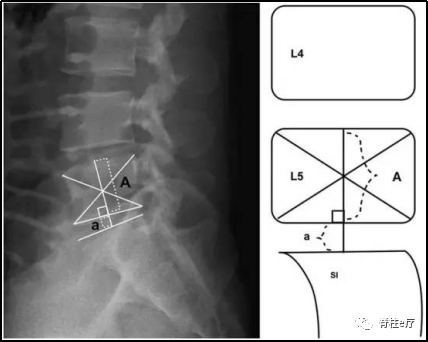

①椎间盘高度指数(disc height index,DHI)

分别由上位椎体和下位椎体的两条对角线确定两者的中点,通过两个中点画一条直线,直线在椎间盘形成的高度是a,在上位椎体形成的高度是A。

DHI=a / A

②矢状位椎体移动度(sagittal range of motion,sROM)

当脊柱极度前屈和向后极度拉伸时,脊柱所运动的最大角度。

sROM=A-B角度

研究证实,DHI与sROM是髓核摘除术后复发的显著预测因素。PELD在摘除破裂髓核的过程中可能会影响脊柱的稳定性,因此脊柱稳定性良好是行PELD的首要条件[29]。

相比于塌陷的椎间盘,高度较高的椎间盘更具有潜在的不稳定性[15],而当椎间盘高度减少50%时,较前相比其稳定性增加[30]。

DHI相对大的椎间盘,术后其稳定性可能进一步降低,因此其术后进行体力活动时更容易突出,导致复发。因此,通过术前计算DHI和sROM可以推测患者术后复发的可能性。